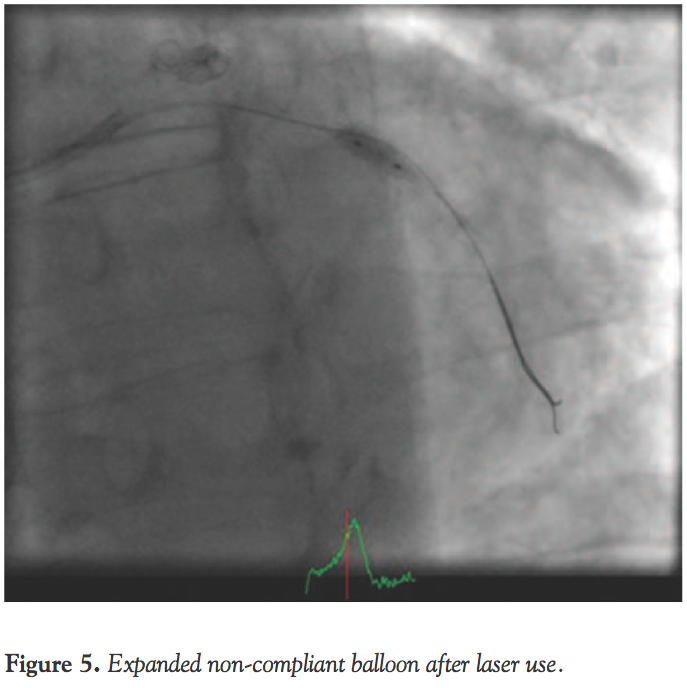

The 1.4 mm laser catheter was used again at 40/40 with concomitant contrast injection while lasing, and this resulted in the catheter passing (Figure 4). Subsequent dilatation was performed with a 3.5 mm non-compliant balloon, which expanded the old under-expanded stent (Figure 5). Subsequently, two DESs (Xience 3.0 x 18 mm and 4.0 x 18 mm) were inserted and postdilated with a 4.0 non-compliant balloon with excellent final results (Figure 6). The patient tolerated the procedure well with no complications and he was monitored on the ward and allowed home in a stable condition on secondary prevention measures and dual antiplatelet therapy.